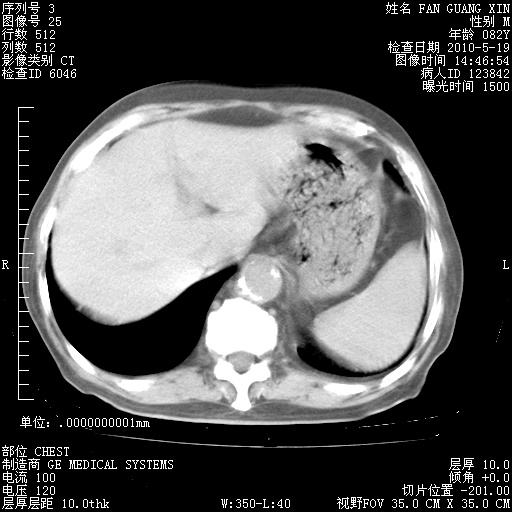

再治疗10天后的肺部CT

再治疗10天后的肺部CT 纵膈窗

从白细胞总数和中性比例看好像合并感染。肺部纹理好像比上次多,支气管炎?其他感染?

阅读此次胸部CT,肺间质渗出性改变较入院时有吸收。目前从体温、白细胞、中性分叶明显增高,肯定存在细菌感染(发生医院感染哦,若无消化道及泌尿系统等感染的依据,肺部感染可能大)。若你院头孢哌酮舒巴坦钠耐药率较高,同意你的方案,若48小时体温仍高,可考虑使用碳青霉稀类抗菌药物,同时可予超声雾化、注意滴数时加大液体量。白蛋白33.30g/L较低哦,需加强营养等支持治疗。